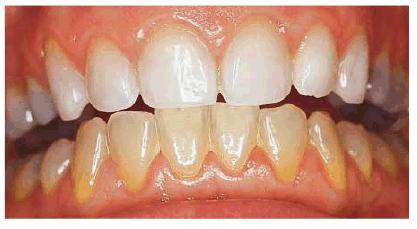

either on an individual tooth or on all teeth (Figures 16-1A, and 16-1B). There are many causes and

Figure 16-1A: An otherwise attractive smile is marred by discolored teeth.

Figure 16-1B: After tooth lightening, the smile is much more pleasing.